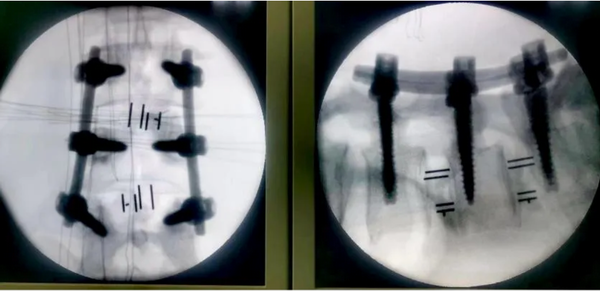

在3D數(shù)字打印技術(shù)輔助下手術(shù)順利完成,術(shù)中影像可見:精準(zhǔn)置釘,徹底減壓,充分植骨融合,退變側(cè)凸滑脫獲得矯正。術(shù)后,患者多年的腰腿疼麻癥狀明顯緩解,對手術(shù)效果滿意。不久,患者將更好的回歸日常生活和生產(chǎn)。